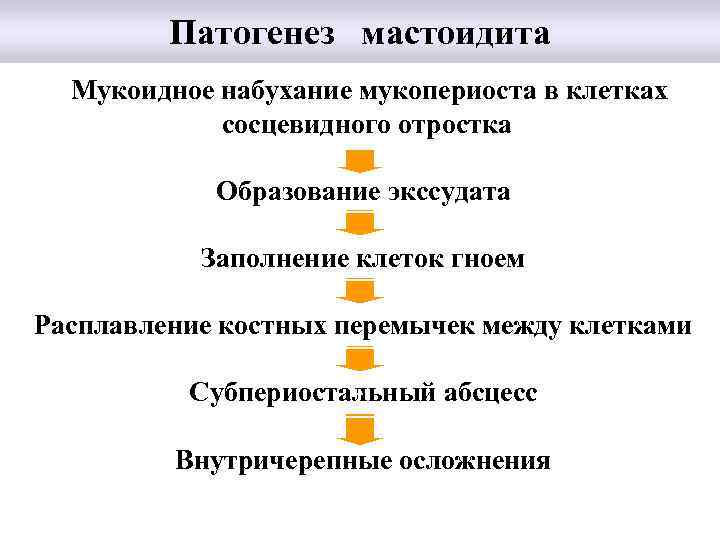

Патогенез мастоидита Мукоидное набухание мукопериоста в клетках сосцевидного отростка Образование экссудата Заполнение клеток гноем Расплавление костных перемычек между клетками Субпериостальный абсцесс Внутричерепные осложнения